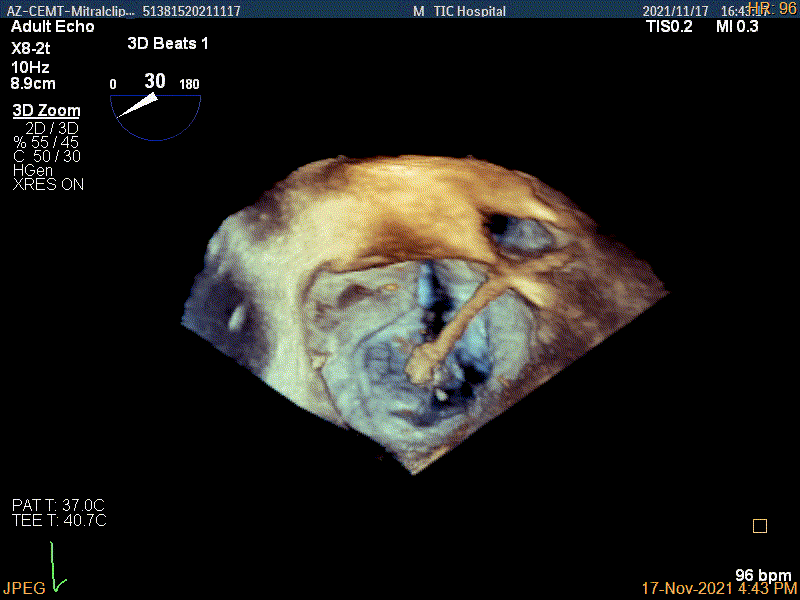

3D-color MV view:源自于交界区的大量反流

3D视图下进夹子并建立trajectory

3D视图打开夹子

Multivue视图下将夹子正对AC区并调节Rotate

X-plane:下夹子尝试捕获靠近AC区脱垂瓣叶

3D证实夹子内侧残余脱垂(P1区)

3Dcolor证实残余分流主要来源于残余脱垂